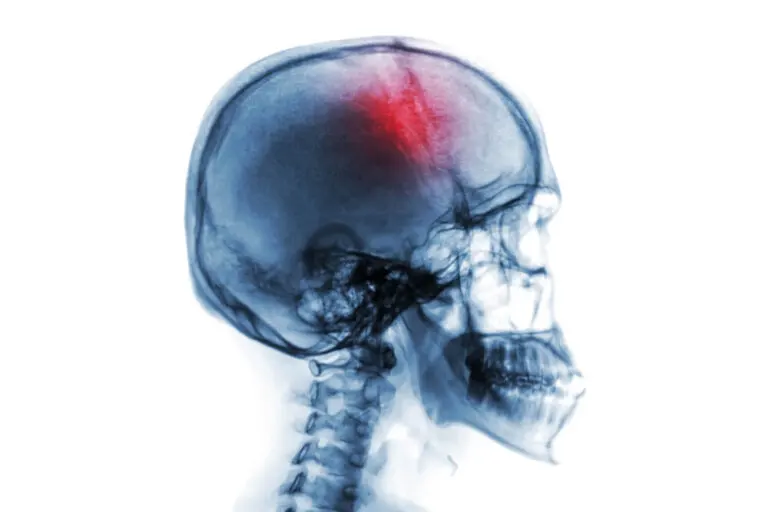

Infarto cerebral: causas y tratamiento

Un infarto cerebral es un paro cerebrovascular que se desencadena por dos posibles razones: un proceso de isquemia o una hemorragia. Durante el proceso isquémico, parte de la masa encefálica muere por un fallo en la irrigación sanguínea.

La isquemia se produce, por lo tanto, cuando el cerebro no recibe la cantidad suficiente de oxígeno. Esta situación se puede producir, por ejemplo, por la presencia de coágulos sanguíneos que bloquean el riego sanguíneo.